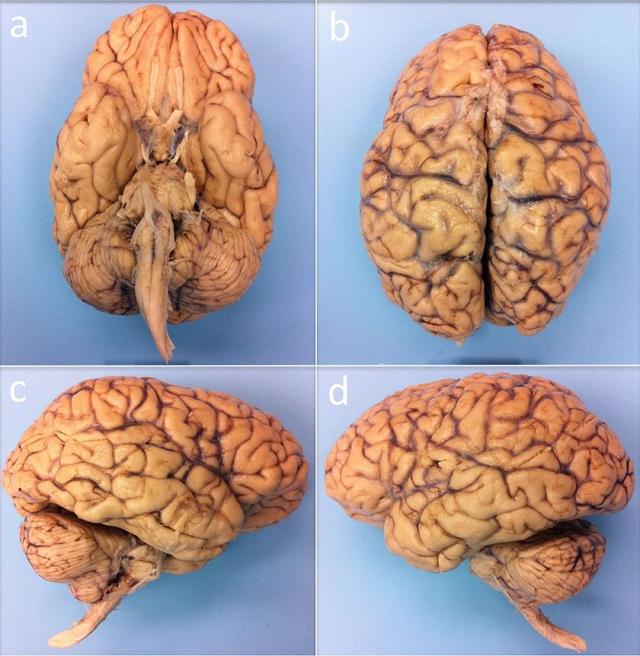

圖 | 體外核磁共振成像的人腦標(biāo)本,下方(a)、上方(b)、右側(cè)(c)和左側(cè)(d)角度(來源:B.L. EDLOW ET AL/BIORXIV.ORG 2019)

而且這個(gè)來自捐獻(xiàn)的大腦樣本被認(rèn)為是健康的,因?yàn)樵撆詻]有神經(jīng)系統(tǒng)疾病病史,死于非神經(jīng)病因。

在掃描開始之前,大腦標(biāo)本已經(jīng)在固定劑中保持了 35 個(gè)月,之后研究人員將大腦標(biāo)本放入一個(gè)定制的球形聚氨酯盒子,以讓大腦保持靜止并讓干擾的氣泡逸出。

然后,牢固包裹的大腦進(jìn)入一臺(tái)7T超強(qiáng)核磁共振掃描儀中,進(jìn)行了長達(dá)近 5 天的掃描成像,獲得了體外完整人腦標(biāo)本前所未有的 100 微米分辨率空間圖像。